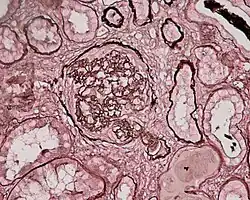

Photomicrograph of a kidney biopsy from a person with crescentic glomerulonephritis showing prominent fibrocellular crescent formation and moderate mesangial proliferation in a glomerulus. Hematoxylin and eosin stain.

Crescentic glomerulonephritis induced by infective endocarditis on PAS staining and immunofluorescence. PAS staining (left) demonstrated circumferential and cellular crescent formation with interstitial nephritis. Immunofluorescence (right) demonstrated C3 positive staining in mesangial area.

Photomicrograph of renal biopsy showing crescent formation and tuft narrowing. Periodic acid silver methenamine stain.

Rapidly progressive glomerulonephritis, also known as crescentic GN, is characterised by a rapid, progressive deterioration in kidney function. People with rapidly progressive glomerulonephritis may present with a nephritic syndrome. In management, steroid therapy is sometimes used, although the prognosis remains poor.[9] Three main subtypes are recognised:[4]: 557–558

Histopathologically, the majority of glomeruli present "crescents". Formation of crescents is initiated by passage of fibrin into the Bowman space as a result of increased permeability of glomerular basement membrane. Fibrin stimulates the proliferation of endothelial cells of Bowman capsule, and an influx of monocytes. Rapid growing and fibrosis of crescents compresses the capillary loops and decreases the Bowman space, which leads to kidney failure within weeks or months.